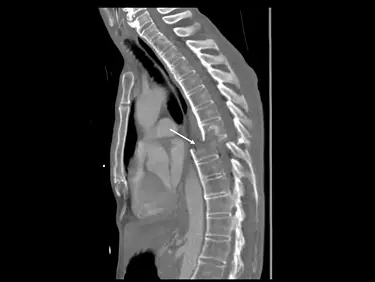

中年男性創傷,矢狀面重組的(sagittal reformatted)電腦斷層影像如下圖,箭號所指異常處最適當的敘述為何?

- 影像為胸部/胸椎的矢狀面重組(sagittal reformatted)CT 影像。

- 箭號指在胸椎部位,可以明顯看到上下相鄰的椎體發生了極度嚴重的水平位移(translation)與錯位(dislocation)。

- 由於椎體的嚴重錯位,原本應該連續的脊椎管(spinal canal)被完全截開。在解剖構造上,這意味著管內的脊髓(spinal cord)受到極大的剪切力,無可避免地會發生完全斷裂。

- 進階影像觀察(Expert Note):若身為專業的醫事放射師,仔細觀察此影像會發現,不僅僅是脊椎,包含前方的胸骨(sternum)、心臟縱隔軟組織,乃至背部的肌肉與皮膚邊緣,都在「同一個水平面」上出現了平齊的斷層位移。在實際臨床影像學中,這種貫穿全體層面的水平位移,非常典型地屬於病患在螺旋CT掃描或影像重組過程中,因呼吸或身體劇烈移動所產生的「階梯假影(stair-step artifact / motion artifact)」。然而,考量到題幹明確給予「創傷(trauma)」的病史,且箭號特地指向脊椎錯位處,此題在考試邏輯上是將其作為「脊椎嚴重錯位導致脊髓斷裂」的經典情境來進行測驗。

- (A) 脊髓橫斷(spinal transection):正確。箭頭指向脊椎的嚴重水平錯位處。在嚴重高能量創傷(如高處墜落、嚴重車禍或重物擠壓)中,這種程度的骨骼與韌帶破壞會直接剪斷脊髓。結合題幹「創傷」病史,這是考官預期的最佳解答。

本題的解題關鍵在於「臨床病史」與「病灶指示」。雖然影像整體因為橫跨全身的水平斷層而帶有移動假影(motion artifact)的視覺特徵,但題幹已明確設定為「中年男性創傷」,且箭頭精準聚焦於胸部脊椎管完全錯開的位置。在強大的外力創傷下,脊椎發生如此巨大的剪切性骨折脫位(fracture-dislocation),必然會導致脊椎管內的脊髓完全斷裂。因此,從臨床診斷與考試命題的雙重邏輯來看,**(A) 脊髓橫斷(spinal transection)**是最符合題意的選項。